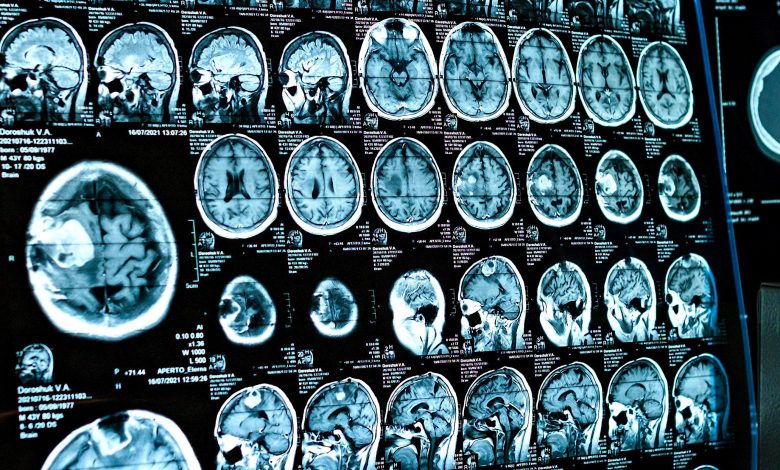

According to a new study by scientists at Stanford University, these changes would typically be more significant after a pandemic period with signs of premature aging. To arrive at this result, the researchers compared the MRI results of 81 adolescents between November 2016 and 2019 (before the pandemic) with those of 82 other adolescents between October 2020 and March 2022 (during the pandemic and after restrictions were lifted). .

After sorting 64 volunteers from both groups and distributing them by age and gender, the researchers found that cortical thinning, hippocampal and amygdala growth were higher in the analyzed group after the pandemic. This process, normal for all adolescents, would accelerate, as if the brain were aging faster.

According to scientists, the difference in brain age will be about three years compared to the group that performed MRI before the pandemic. “We didn’t expect such a large increase given that the incarceration lasted less than a year,” said Jan Gottlieb, professor of psychology at Stanford University and lead author of the study.